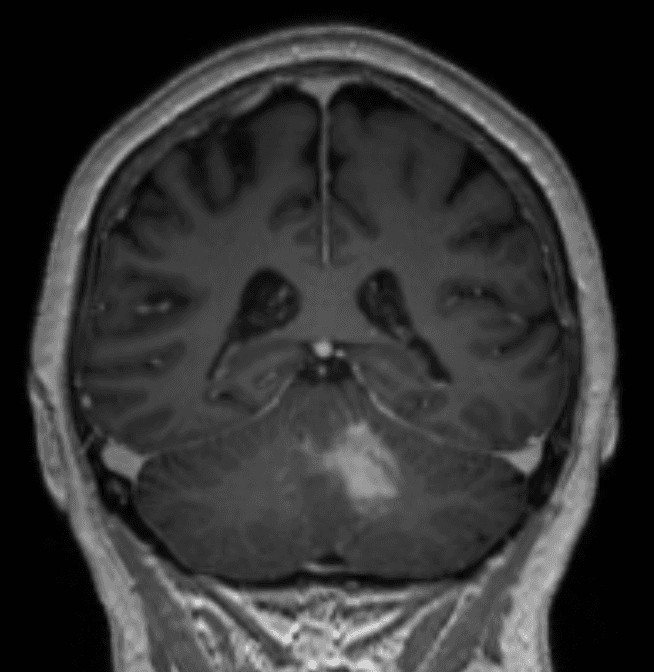

Ha effettuato una risonanza magnetica che ha mostrato una lesione omogenea con contrasto adiacente al quarto ventricolo nel tessuto cerebellare e un edema perifocale moderato (Figure 1–2). I peduncoli del tronco encefalico e cerebellari non erano coinvolti. Non sono stati rilevati segni di emorragia o ischemia.

Figura 2. Questa vista assiale mostra un'iperintensità periventricolare T2, che mostra un edema perifocale moderato. Il lume del quarto ventricolo è ancora aperto, permettendo il passaggio del liquido cerebrospinale. Si prega di notare l'assenza di un effetto di massa significativo o di segni di ernia transtentoriale.Se non trattata, questa lesione porterebbe infine a idrocefalo oclusivo, coma e la morte. Se la dimensione aumentasse, i sintomi cerebellari aumenterebbero (ad esempio, disartria, tremore intenzionale, attassia) e i sintomi del tronco encefalico probabilmente peggiorerebbero (deficit dei nervi cranici, ad esempio, difficoltà a deglutire, paresi, disregolazione vegetativa, coma).